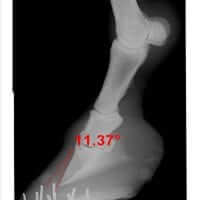

Navicular Disease In the Horse

Equine Navicular Disease has many names, including Navicular Syndrome, caudle heel pain as well as podotrochleosis.  The condition is all too common to many horse owners, unfortunately, and can significantly impact performance, general movement and overall quality of life due to pain generally located in the heel region of the front feet.  Navicular Syndrome can be difficult to manage, especially in the advanced stage, but through a combination of approaches, including nutrion and herbs, the outcome for the patient can be improved.